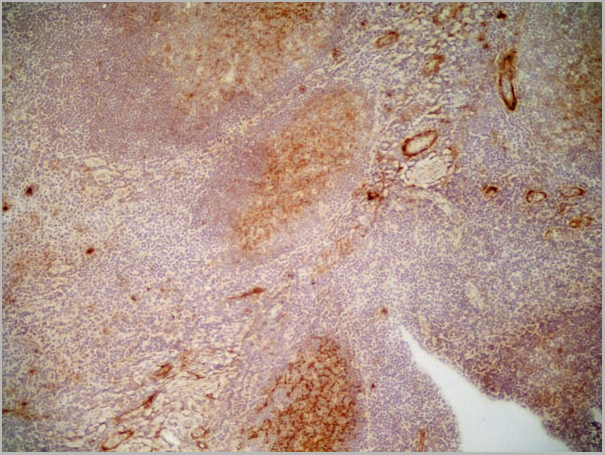

(Immunoperoxidase staining of human tonsil cryosection with Mouse anti Human CD36 antibody, clone SMø followed by the HISTAR detection system . High power SMθ)